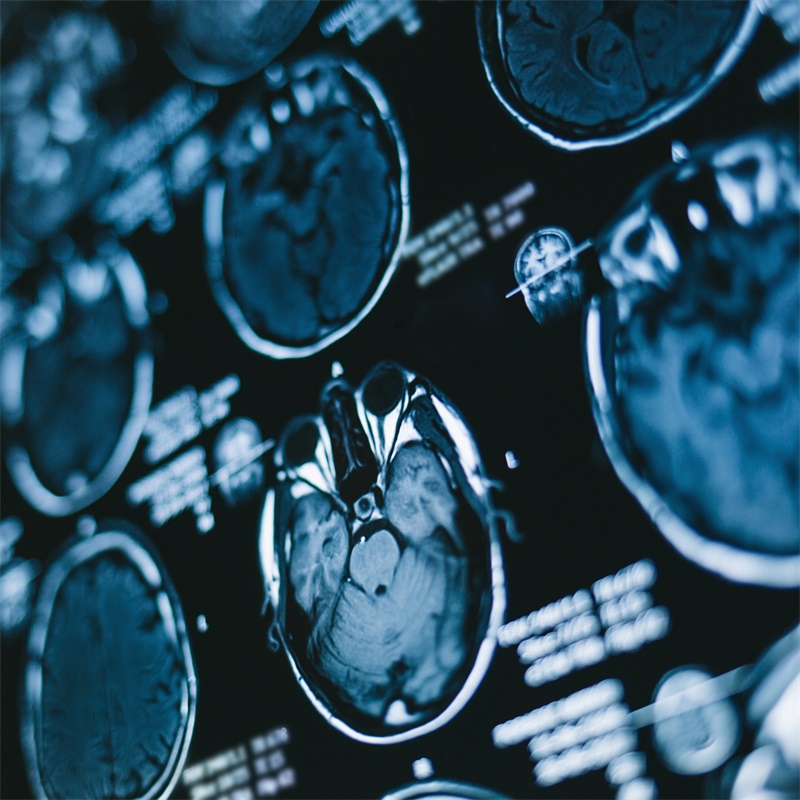

对急性卒中进行合适的治疗是一项与时间的竞赛。大多数急性缺血性脑卒中是由于血栓栓塞阻塞颅内动脉所致。当脑血流量(CBF)下降到某一水平以致不能维持组织的存活时,缺血损伤的计时就已经开始了。缺血损伤的程度取决于不同神经元对缺血的耐受力及局部相对脑血流量。虽然对缺血区域进行再灌注可减轻缺血的程度,但它同时也会造成神经元的损伤。这个过程被称为再灌注损伤。因此对急性卒中的合适治疗需是在减轻缺血损伤的同时还应尽可能减小再灌注损伤的程度。

大面积半球梗死的患者的预后很差。恶性脑梗死可以由颈内动脉末端或大脑中动脉近端主干阻塞引起,这一点在动物实验及临床研究中得到了证实。损伤通常与脑水肿和逐渐增高的颅内压有关,较终将形成脑疝,导致死亡。根据临床研究的发展和目前有限的治疗方法,去骨瓣减压术的作用得到了重新的认识。减压术可以使颅内压明显减低,限制梗死区域的扩大。颅内压和机械压的下降使脑灌注压升高,导致脑血流增加。

实验证明手术时机是至关重要的。动物模型在大脑中动脉阻塞后1~4小时内进行减压手术结果会促进神经功能的恢复,减小梗死范围临床研究显示,发病后平均21小时内进行手术与发病后39小时进行手术比较,死亡率明显减小。年龄对手术结果的影响目前还不清楚但有证据显示年轻人手术效果较老年人更好。